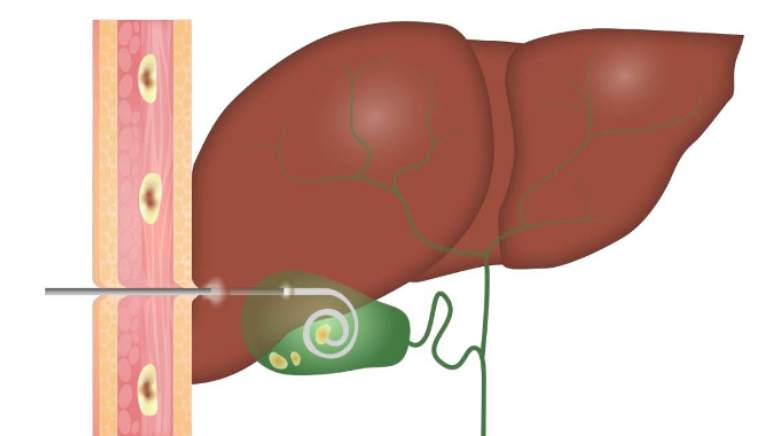

Figure 11: CT imaging of pyogenic liver abscess with percutaneous drainage. CT-guided aspiration is the preferred approach for both diagnostic confirmation and therapeutic drainage.

Figure 12: CT-guided drainage of liver abscesses. (A) CT revealing multiple hypodense lesions in the right hepatic lobe; (B) follow-up showing catheter in place and decrease in abscess size.